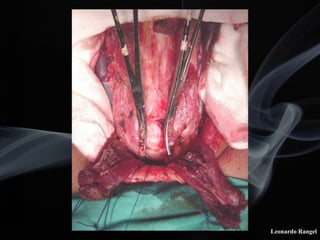

! A incisão de abertura superior da laringe deve

ser exatamente ao nível do pecíolo.

! No lado do tumor, a mucosa subglótica ao nível

da cricóide, deve ser descolada juntamente com

o pericôndrio interno.

! É necessário a preservação do nervo laríngeo

(recorrente) e de uma aritenóide no lado

normal.

! A aproximação da cartilagem cricóide ao osso

hióide deve ser efetuada num mesmo nível.

LPSC

sumário dos pontos chaves